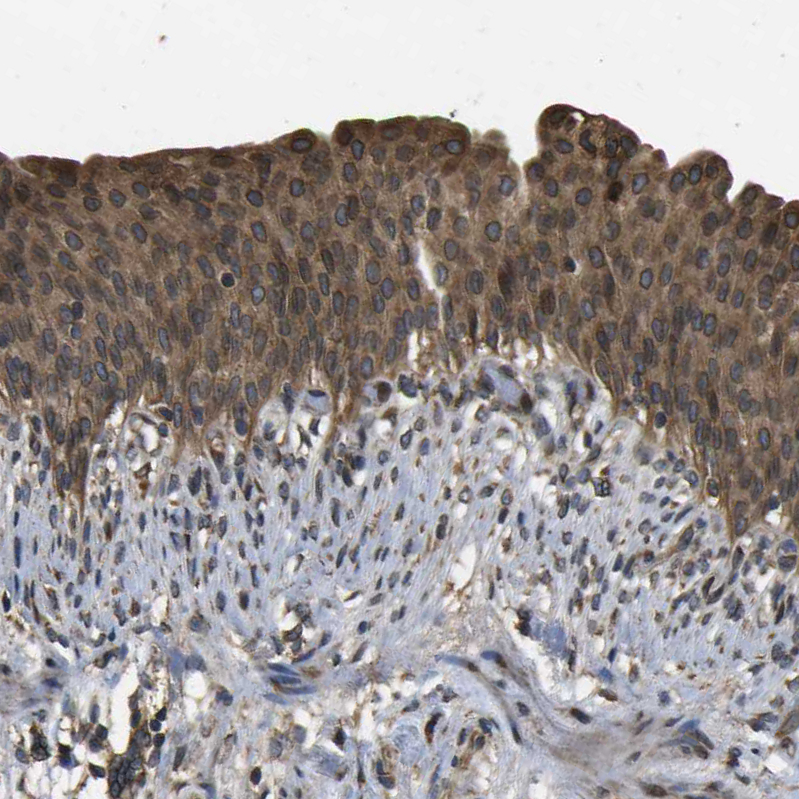

Immunohistochemical staining of human urinary bladder shows strong cytoplasmic positivity in urothelial cells.